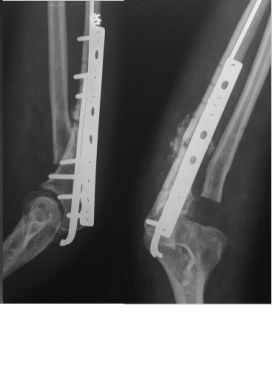

此处用钢板失败率极高,取出内固定后应力集中,(外侧孔或坚强固定内固定的应力遮挡影响局部的骨质、钢板下皮质骨吸收。)都是断裂原因,此病人明显有孔。

点评:可能的原因手术不当,剥离过多而没有植骨;钢丝多此一举;康复不利关节僵硬。骨质疏松提示功能不好。取出钢板骨断裂,取出后片子显示骨折愈合不良;因为功能差桡骨头切除

教训:新鲜孟氏骨折尺骨复位桡骨头即可复位,必要时修复外侧韧带。早期功能锻炼很重要。近关节的骨折愈合不好关节僵硬取出内固定后更容易断裂;不熟悉的方法要有人指导或不用。钢丝代替环韧带有适应症,不适合新鲜骨折。